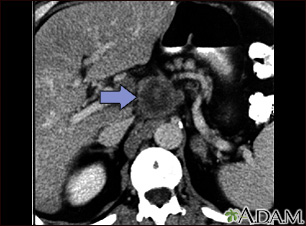

An abdominal CT scan is an imaging test that uses x-rays to create cross-sectional pictures of the belly area. CT stands for computed tomography.

The abdominal CT scan may show some cancers, including:

- Pancreatic cancer